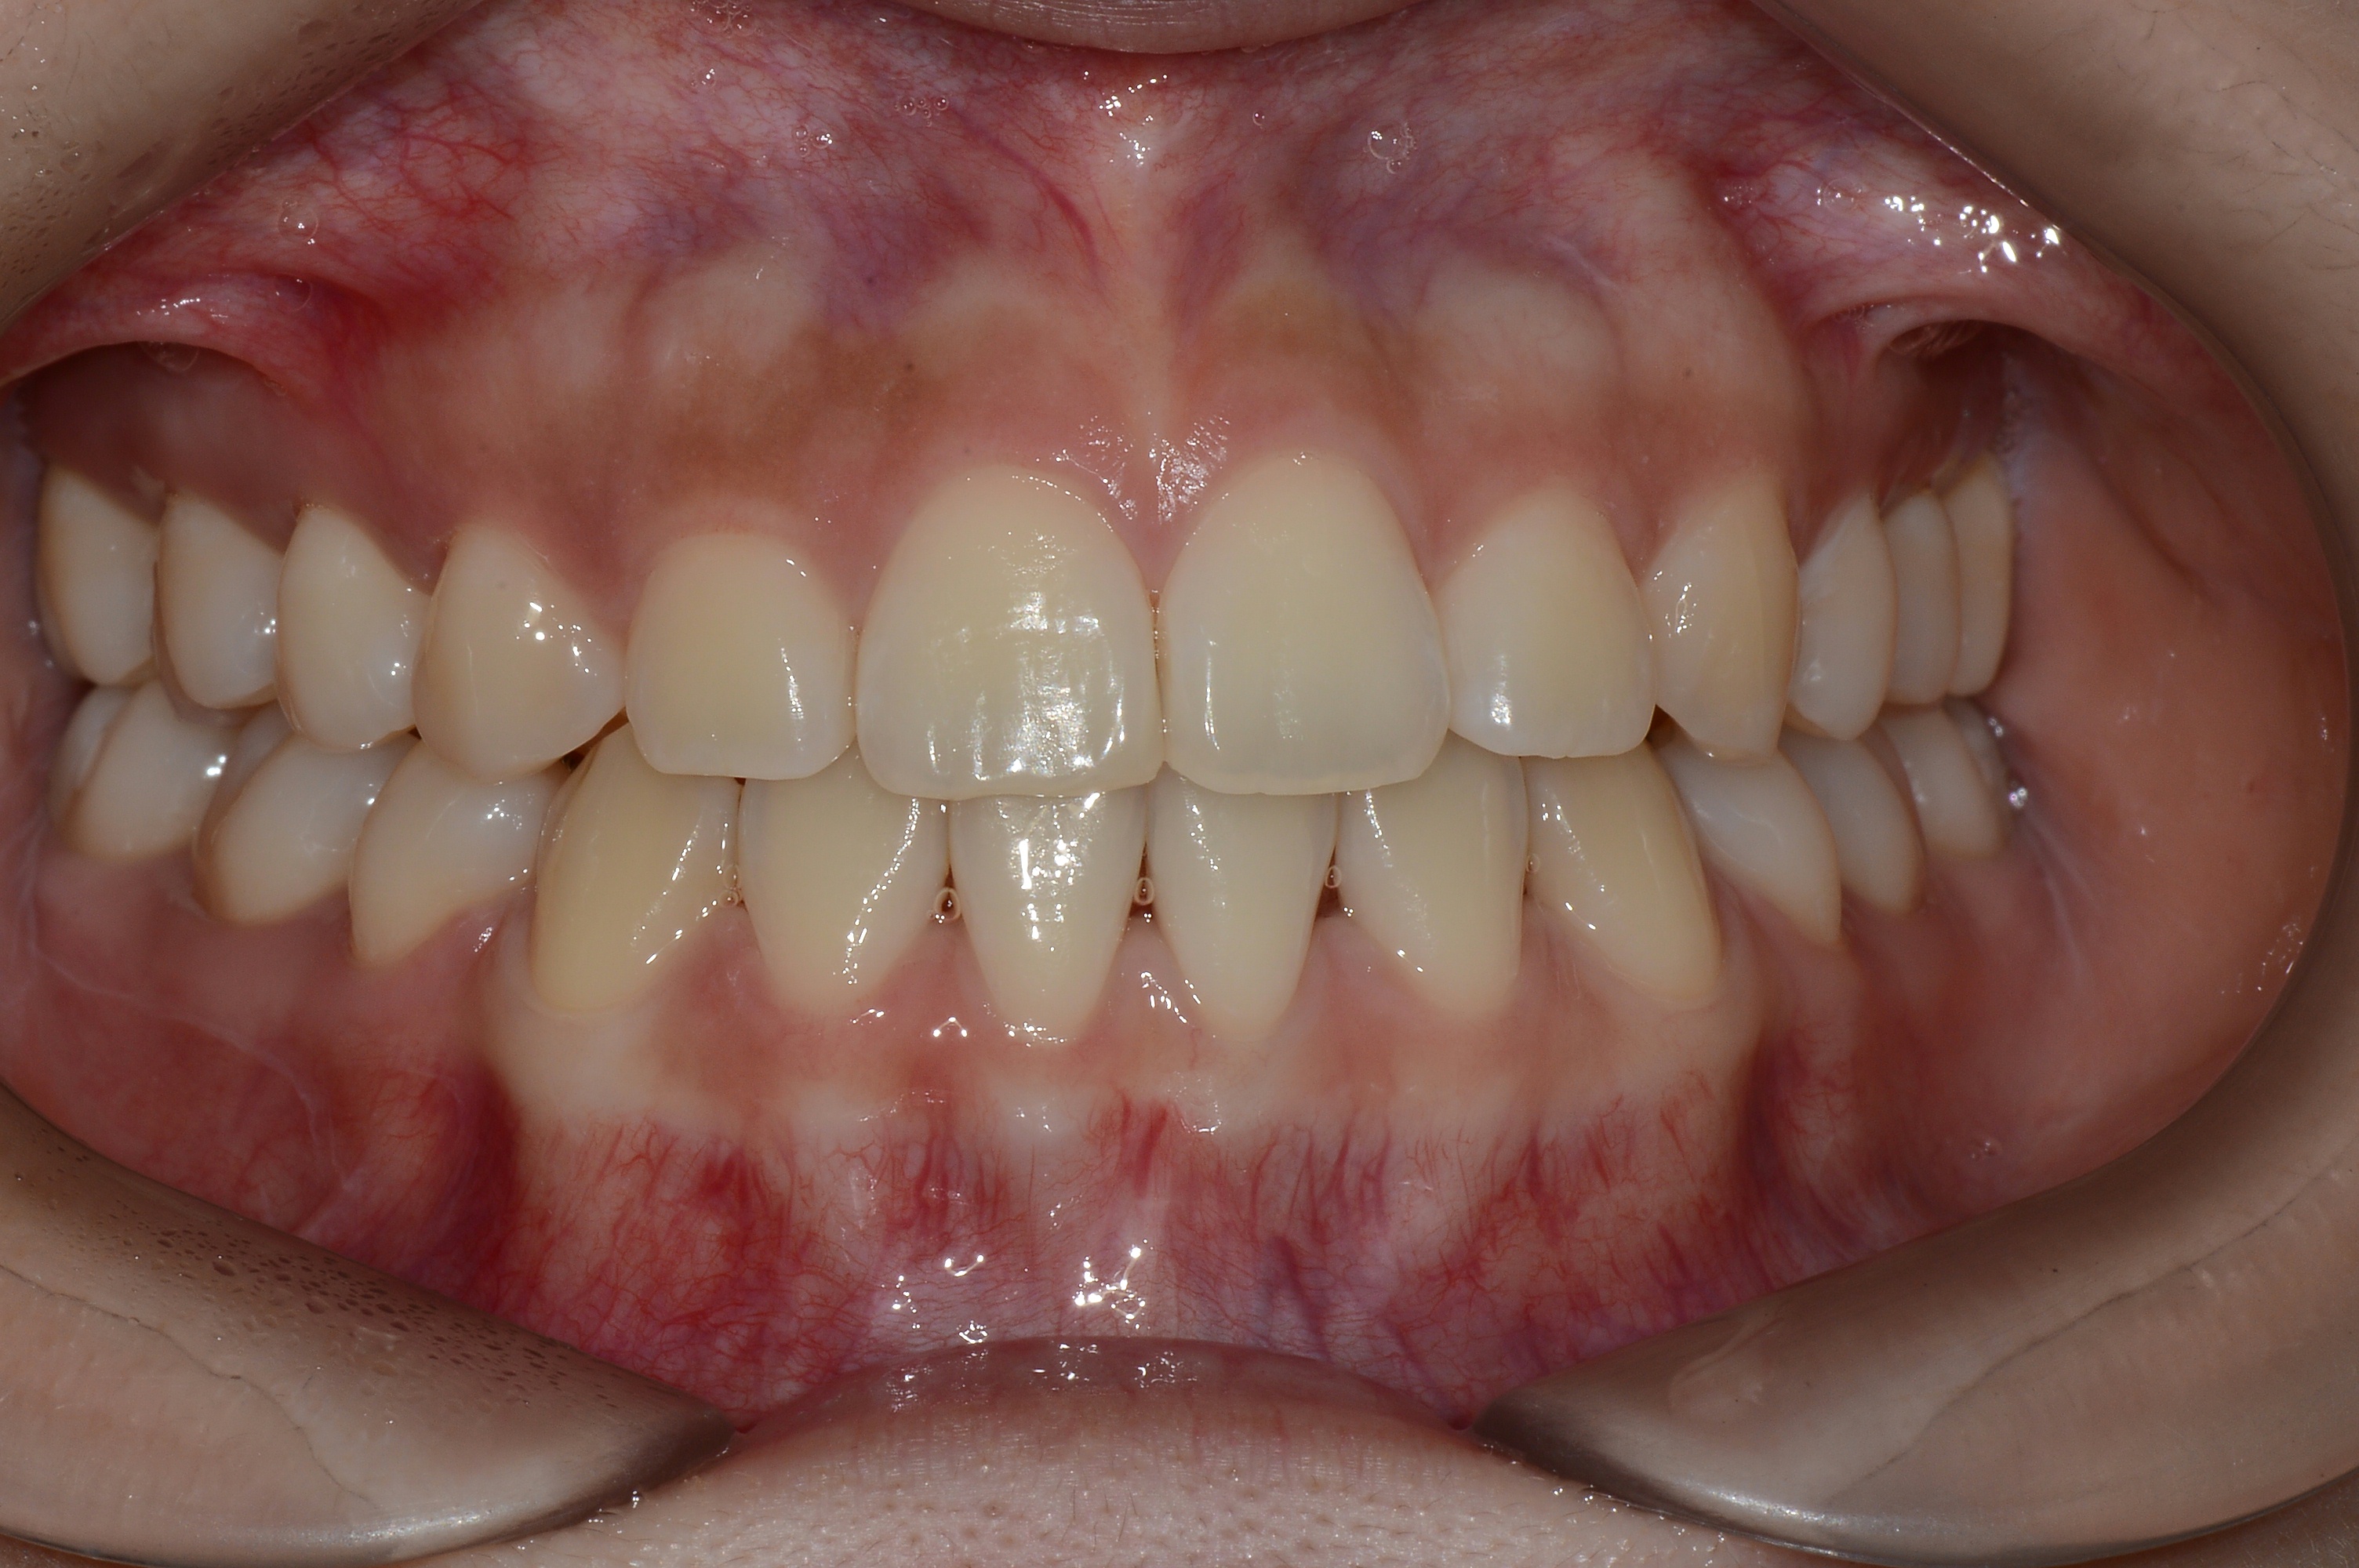

치료 후 사진입니다.